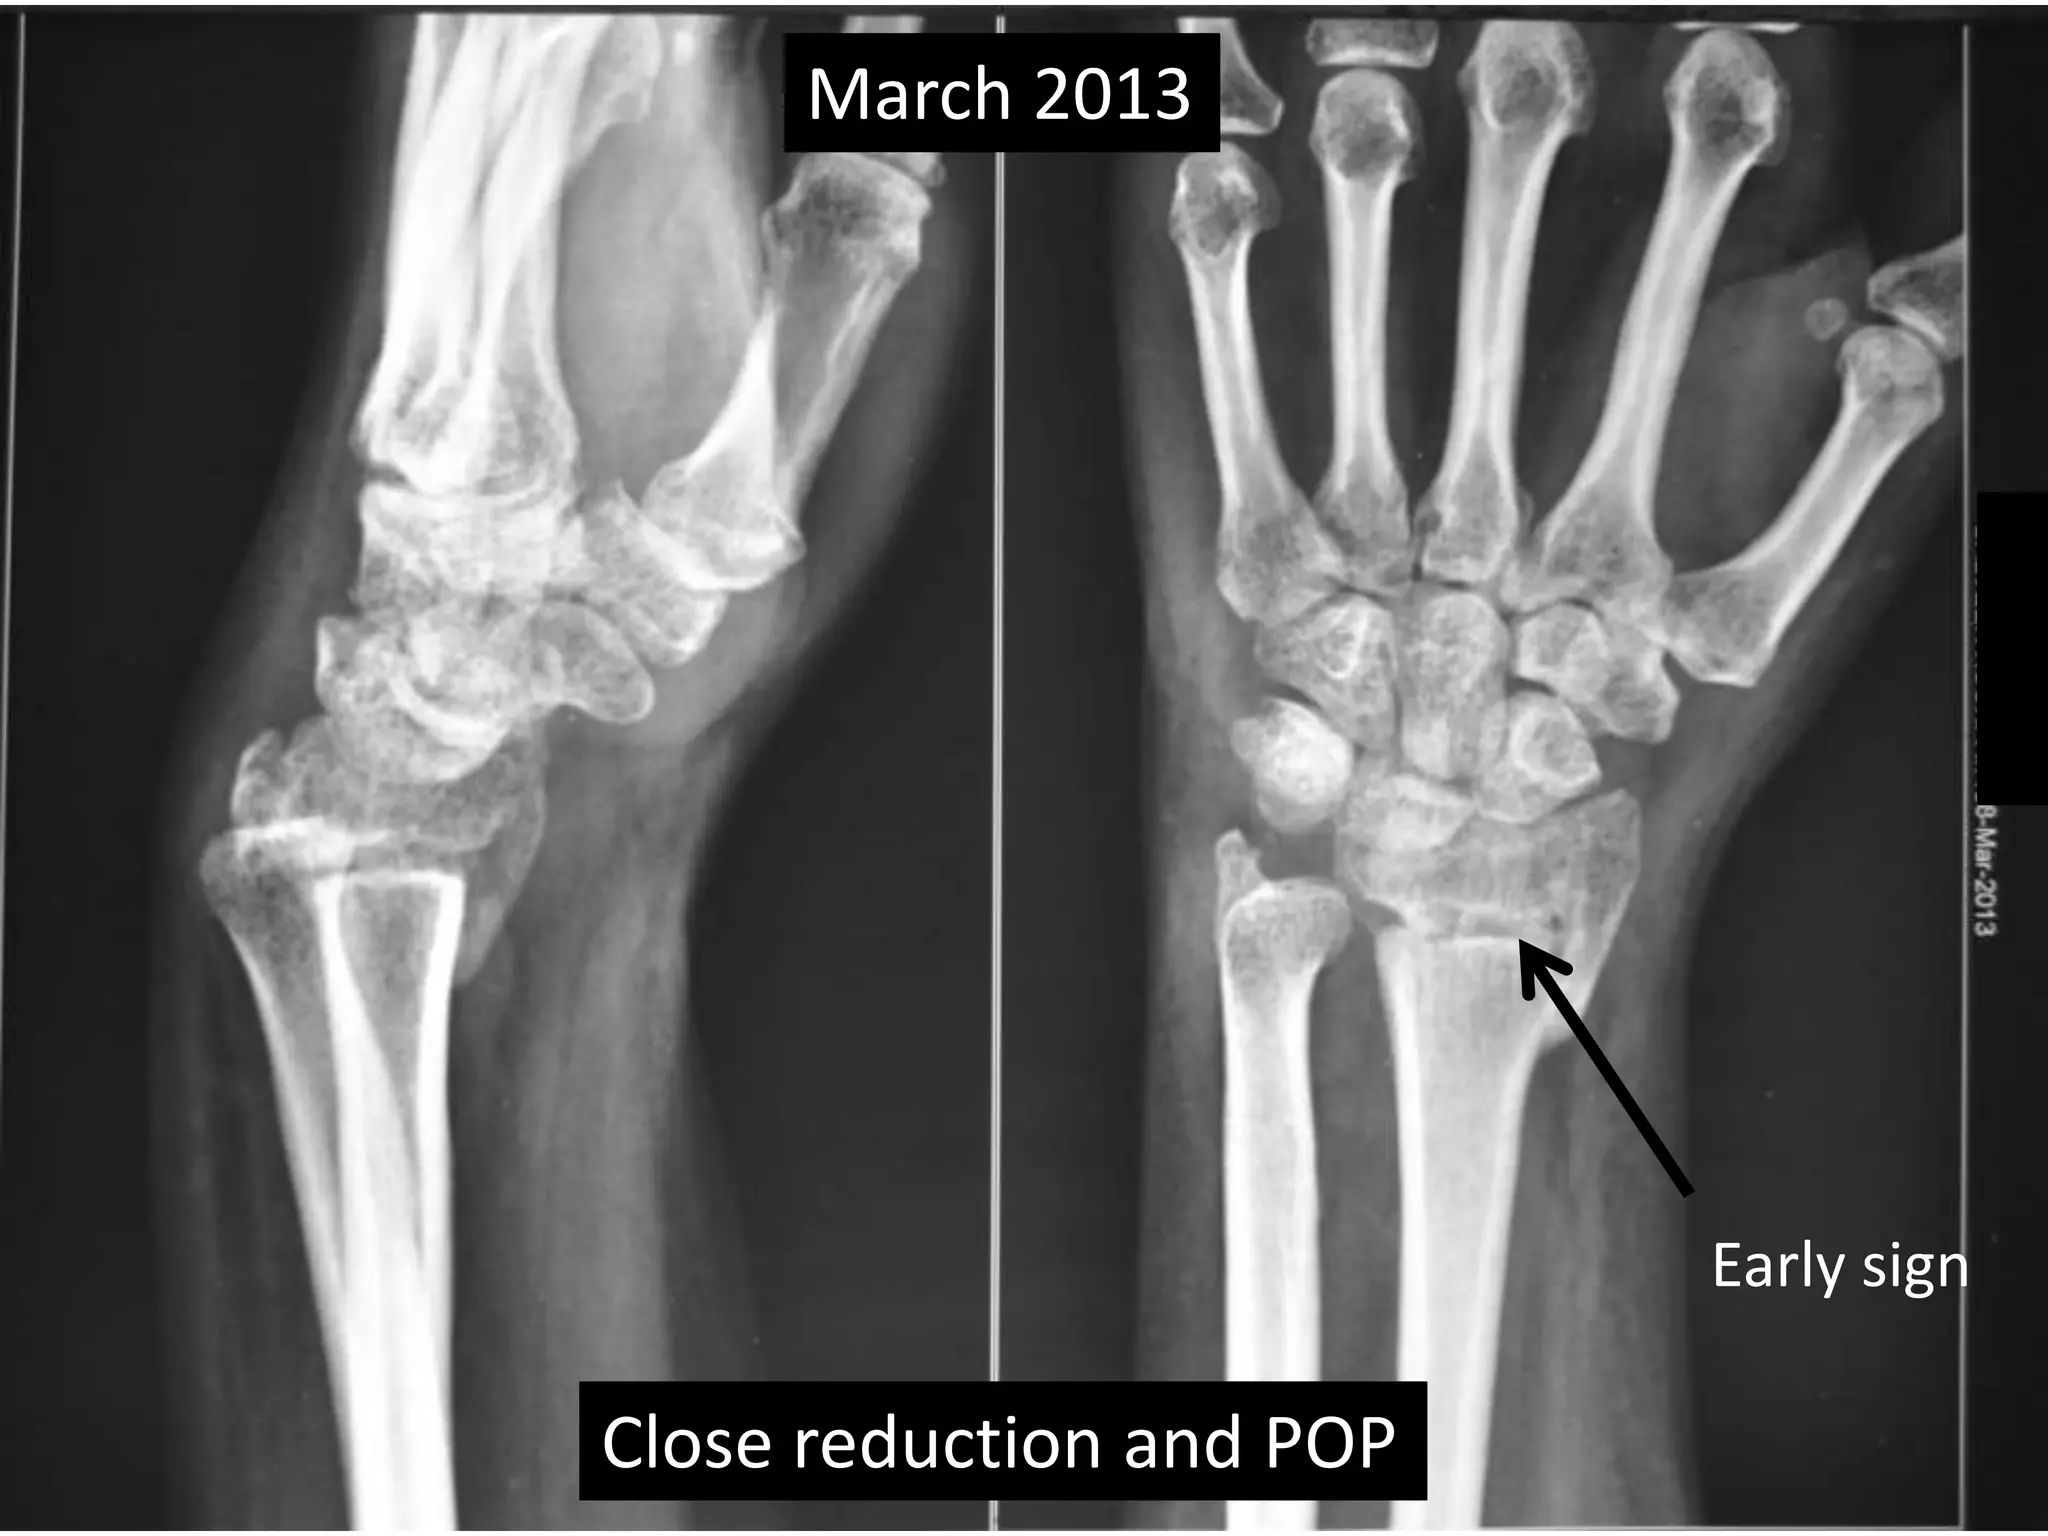

Case one

• 42 years old female.

• Low energy trauma.

• Fracture lower end radius

• Treated conservatively by closed reduction

and pop casting in Dec 2012.

March 2013

Close reduction and POP

Early sign

Case one •42 years old female. • Low energy trauma. • Fracture lower end radius • Treated conservatively by closed reduction and pop casting in Dec 2012.

March 2013 Closereduction and POP Early sign